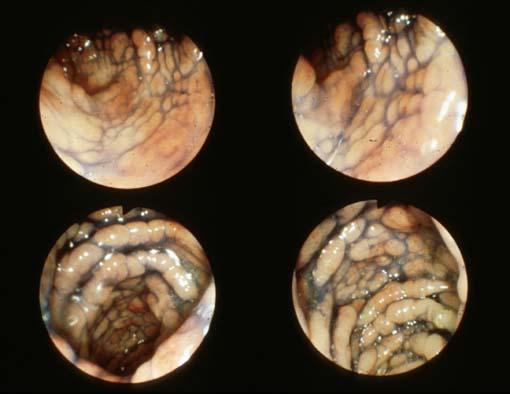

Cronkhite-Canada综合症

伴有食道癌和胃癌的Cronkhite-Canada综合症

疾病(病理主体)的分类

肿瘤样病变/Cronkhite-Canada综合症

部位(按器官分)

大肠/占据大肠的2个以上区域

检查方法

内窥镜

肿瘤最大直径

10~14

多发性肿瘤(同一器官)

无

多重性肿瘤(多个器官)

有(同时性)